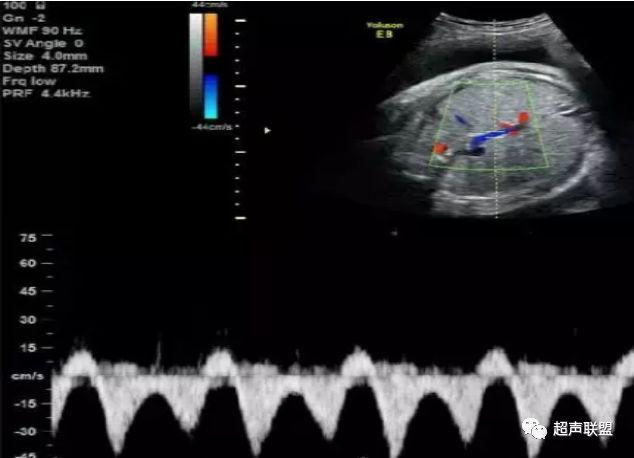

1 胎儿脐动脉测定

缺氧首先出现的变化是舒张末期血流降低,S/D值、RI值和PI值升高。当缺氧进入再分配晚期时,可逐渐出现舒张期血流减少、舒张期血流缺失。失代偿期出现脐动脉血液逆流,舒张期血流倒置。

图1 正常脐动脉血流频谱

图2 脐动脉舒张期血流消失或反向